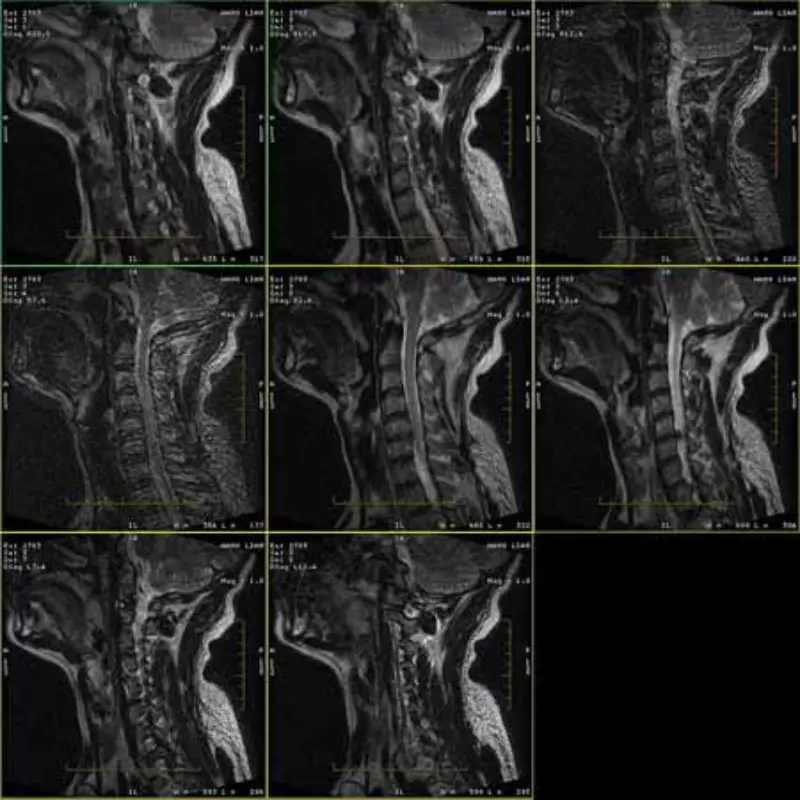

FRFSE மற்றும் GRE நெறிமுறைகளின் படங்கள் பேய் மற்றும் சில நேரங்களில் குறைந்த SNR படங்கள் ஒரு தொடரில் தோன்றும். ஆனால் SE நெறிமுறை படங்கள் இயல்பானவை.

1. இந்த கலைப்பொருட்கள் FRFSE மற்றும் GRE நெறிமுறைகளின் படத்தில் மட்டுமே நிகழ்கின்றன, ஆனால் SE நெறிமுறை

படங்கள் ஒருபோதும் தோன்றாது. ஹெட் SPT விரைவுச் சரிபார்ப்பைச் செய்யுங்கள், ஹெட் SNR ஓரளவு உள்ளது (சுமார் 8.2).